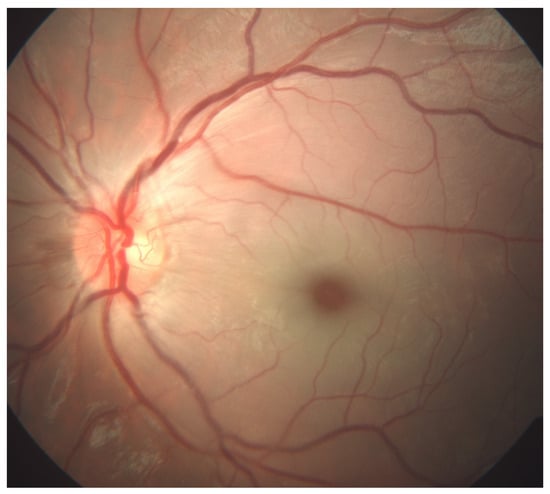

Optical coherence tomography angiography (OCTA, OptoVue Avanti XR version 2016.1.0.26, Optovue Inc., Fremont, California, United States of America) revealed normal retinal circulation in the RE, while the LE showed disruption of the superficial and deep capillary plexus with decreased vascular perfusion. Optical coherence tomography (OCT) displayed the hyper-reflectivity of the inner and the hypo-reflectivity of the outer retinal layers with increased central macular thickness and a loss of organized layer structure (Figure 2).

Figure 2. Optical coherence tomography angiography (OCTA, OptoVue Avanti XR version 2016.1.0.26, Optovue Inc., Fremont, California, United States of America) image of a six-year-old patient’s left eye with central retinal artery occlusion: disruption of the superficial and deep capillary plexus with decreased vascular perfusion. Optical coherence tomography (OCT) displayed hyper-reflectivity of inner and hypo-reflectivity of outer retinal layers with increased central macular thickness and loss of organized layer structure.